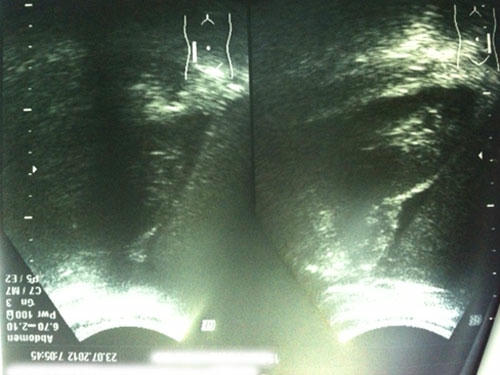

Kết quả siêu âm bụng cho thấy bệnh nhân H. bị vỡ gan |

Bệnh nhân nhập viện vẫn tỉnh táo, huyết động ổn định nhưng khi siêu âm bụng, các bác sĩ xác định bệnh nhân bị vỡ gan hạ phân thùy IV. Bệnh nhân được chỉ định điều trị nội khoa để bảo tồn phần gan đã vỡ. Sức khỏe bệnh nhân đã dần ổn định.